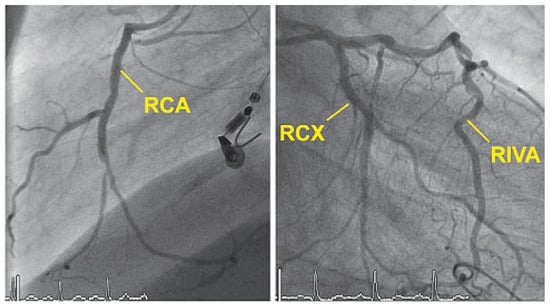

Up to ten percent of acute coronary syndromes occur during or shortly after physical exercise. In fact, physical exertion of more than 4 METs transiently increases the risk for myocardial infarction which remains elevated until an hour afterwards. Th...